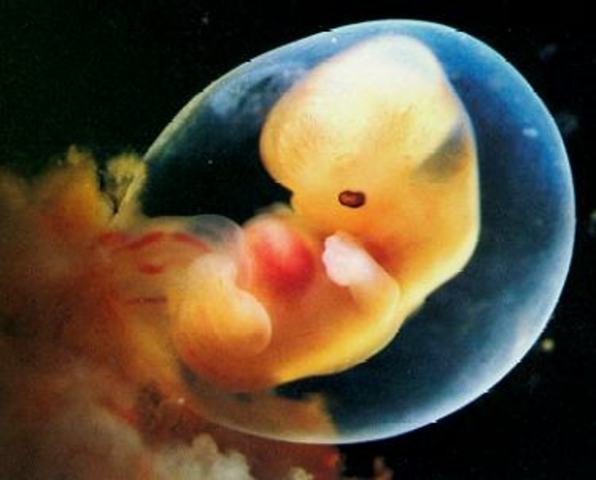

• DESARROLLO FETAL: SEMANA 2 Y 3

DESARROLLO FETAL: SEMANA 2 Y 3

En estas semanas se ha completado implantación del embrión humano. Su crecimiento será muy rápido a partir de este momento. El embrión aparece al centro, como un disco bilaminar y se encuentra entre dos cavidades: el amnios y el saco vitelino. Por fuera, encontramos al trofoblasto que va a formar la parte fetal de la placenta.